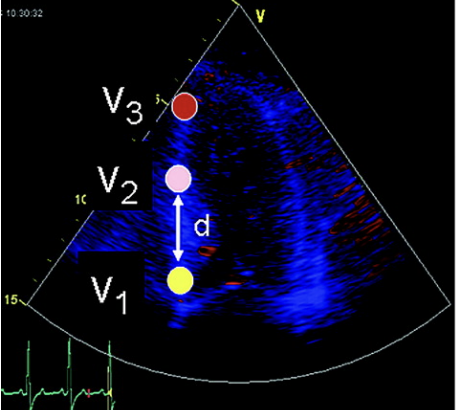

Tissue doppler strain rate

based on difference in TDI velocity between sample volumes divided by distance between them

formula for strain rate

SR =(V1- V2)/D (s-1)